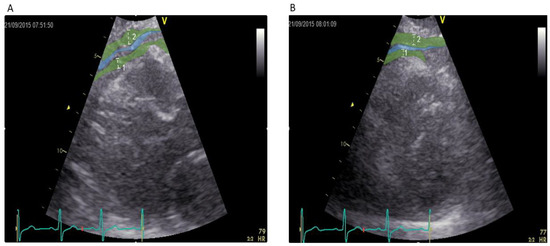

2.5. Echocardiographic Measurement of Epicardial Fat Thickness

- Iacobellis, G.; Assael, F.; Ribaudo, M.C.; Zappaterreno, A.; Alessi, G.; Di Mario, U.; Leonetti, F. Epicardial fat from echocardiography: A new method for visceral adipose tissue prediction. Obes. Res. 2003, 11, 304–310. [Google Scholar] [CrossRef] [PubMed]

- Iacobellis, G.; Willens, H.J. Echocardiographic epicardial fat: A review of research and clinical applications. J. Am. Soc. Echocardiogr. Off. Publ. Am. Soc. Echocardiogr. 2009, 22, 1311–1319. [Google Scholar] [CrossRef] [PubMed]